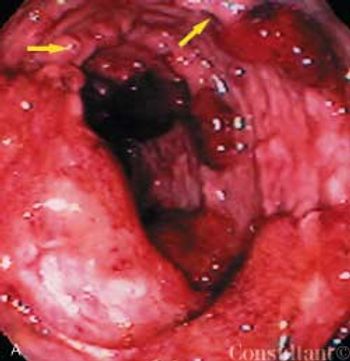

For 6 weeks, a 29-year-old previously healthy man had between 10 and 15 episodes daily of small-volume bloody diarrhea with intermittent paraumbilical pain. Anorexia and the loss of 25 lb accompanied the diarrhea. The patient had no significant medical history, took no medications, had not traveled recently, and had no contact with sick persons. He denied fever, chills, nausea, vomiting, and all other symptoms.